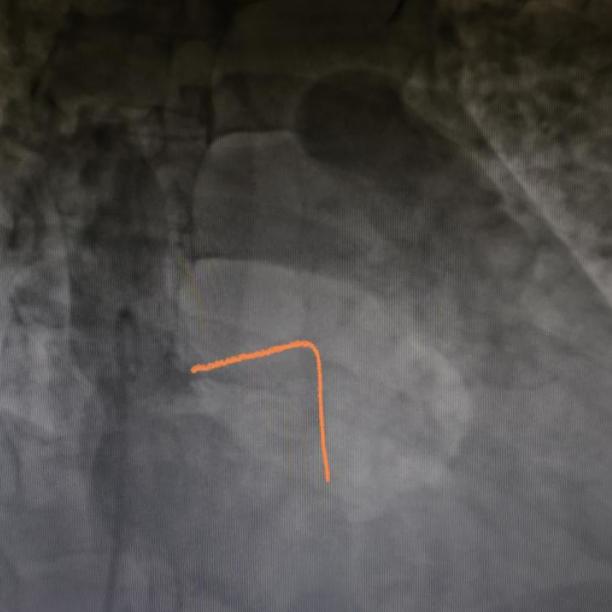

起搏器旋入

进入对接栓模式并进行张力测试

起搏器释放